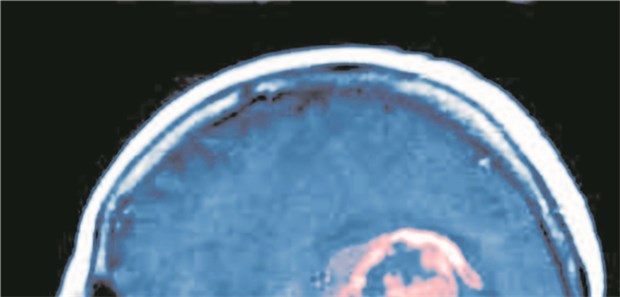

Gehirnblutung: Unter NOAK starben relativ 25 Prozent weniger Insult-Patienten als unter VKA.

Neu ist besser

Keine Angst vor Hirnblutung unter NOAK!